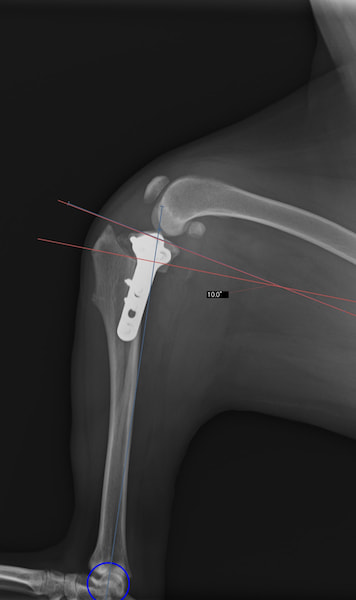

本症例は、走った後に左後肢を挙上していることを主訴に来院されました。触診時に左膝関節のクリック音を聴取、レントゲン検査にて左脛骨の前方変位が認められました。術中に、前十字靱帯の断裂及び内側半月板の損傷、内側の軟部組織の顕著な腫脹を確認。半月板切除、TPLOを実施しました。周囲組織への炎症の波及もあったため回復に時間を要しておりますが、徐々に跛行頻度は減少傾向にあり、現在も経過観察中です。術前に約29°あったTPAは術後に約10°まで矯正されました。

手術前後のTPA(脛骨高平部の角度)を測定しています。

約29°から約10°へ矯正されています。